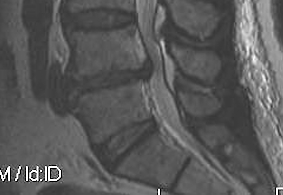

MRI

T2 Sagittal - myelogram

T1 Axial - see nerve root against white fat